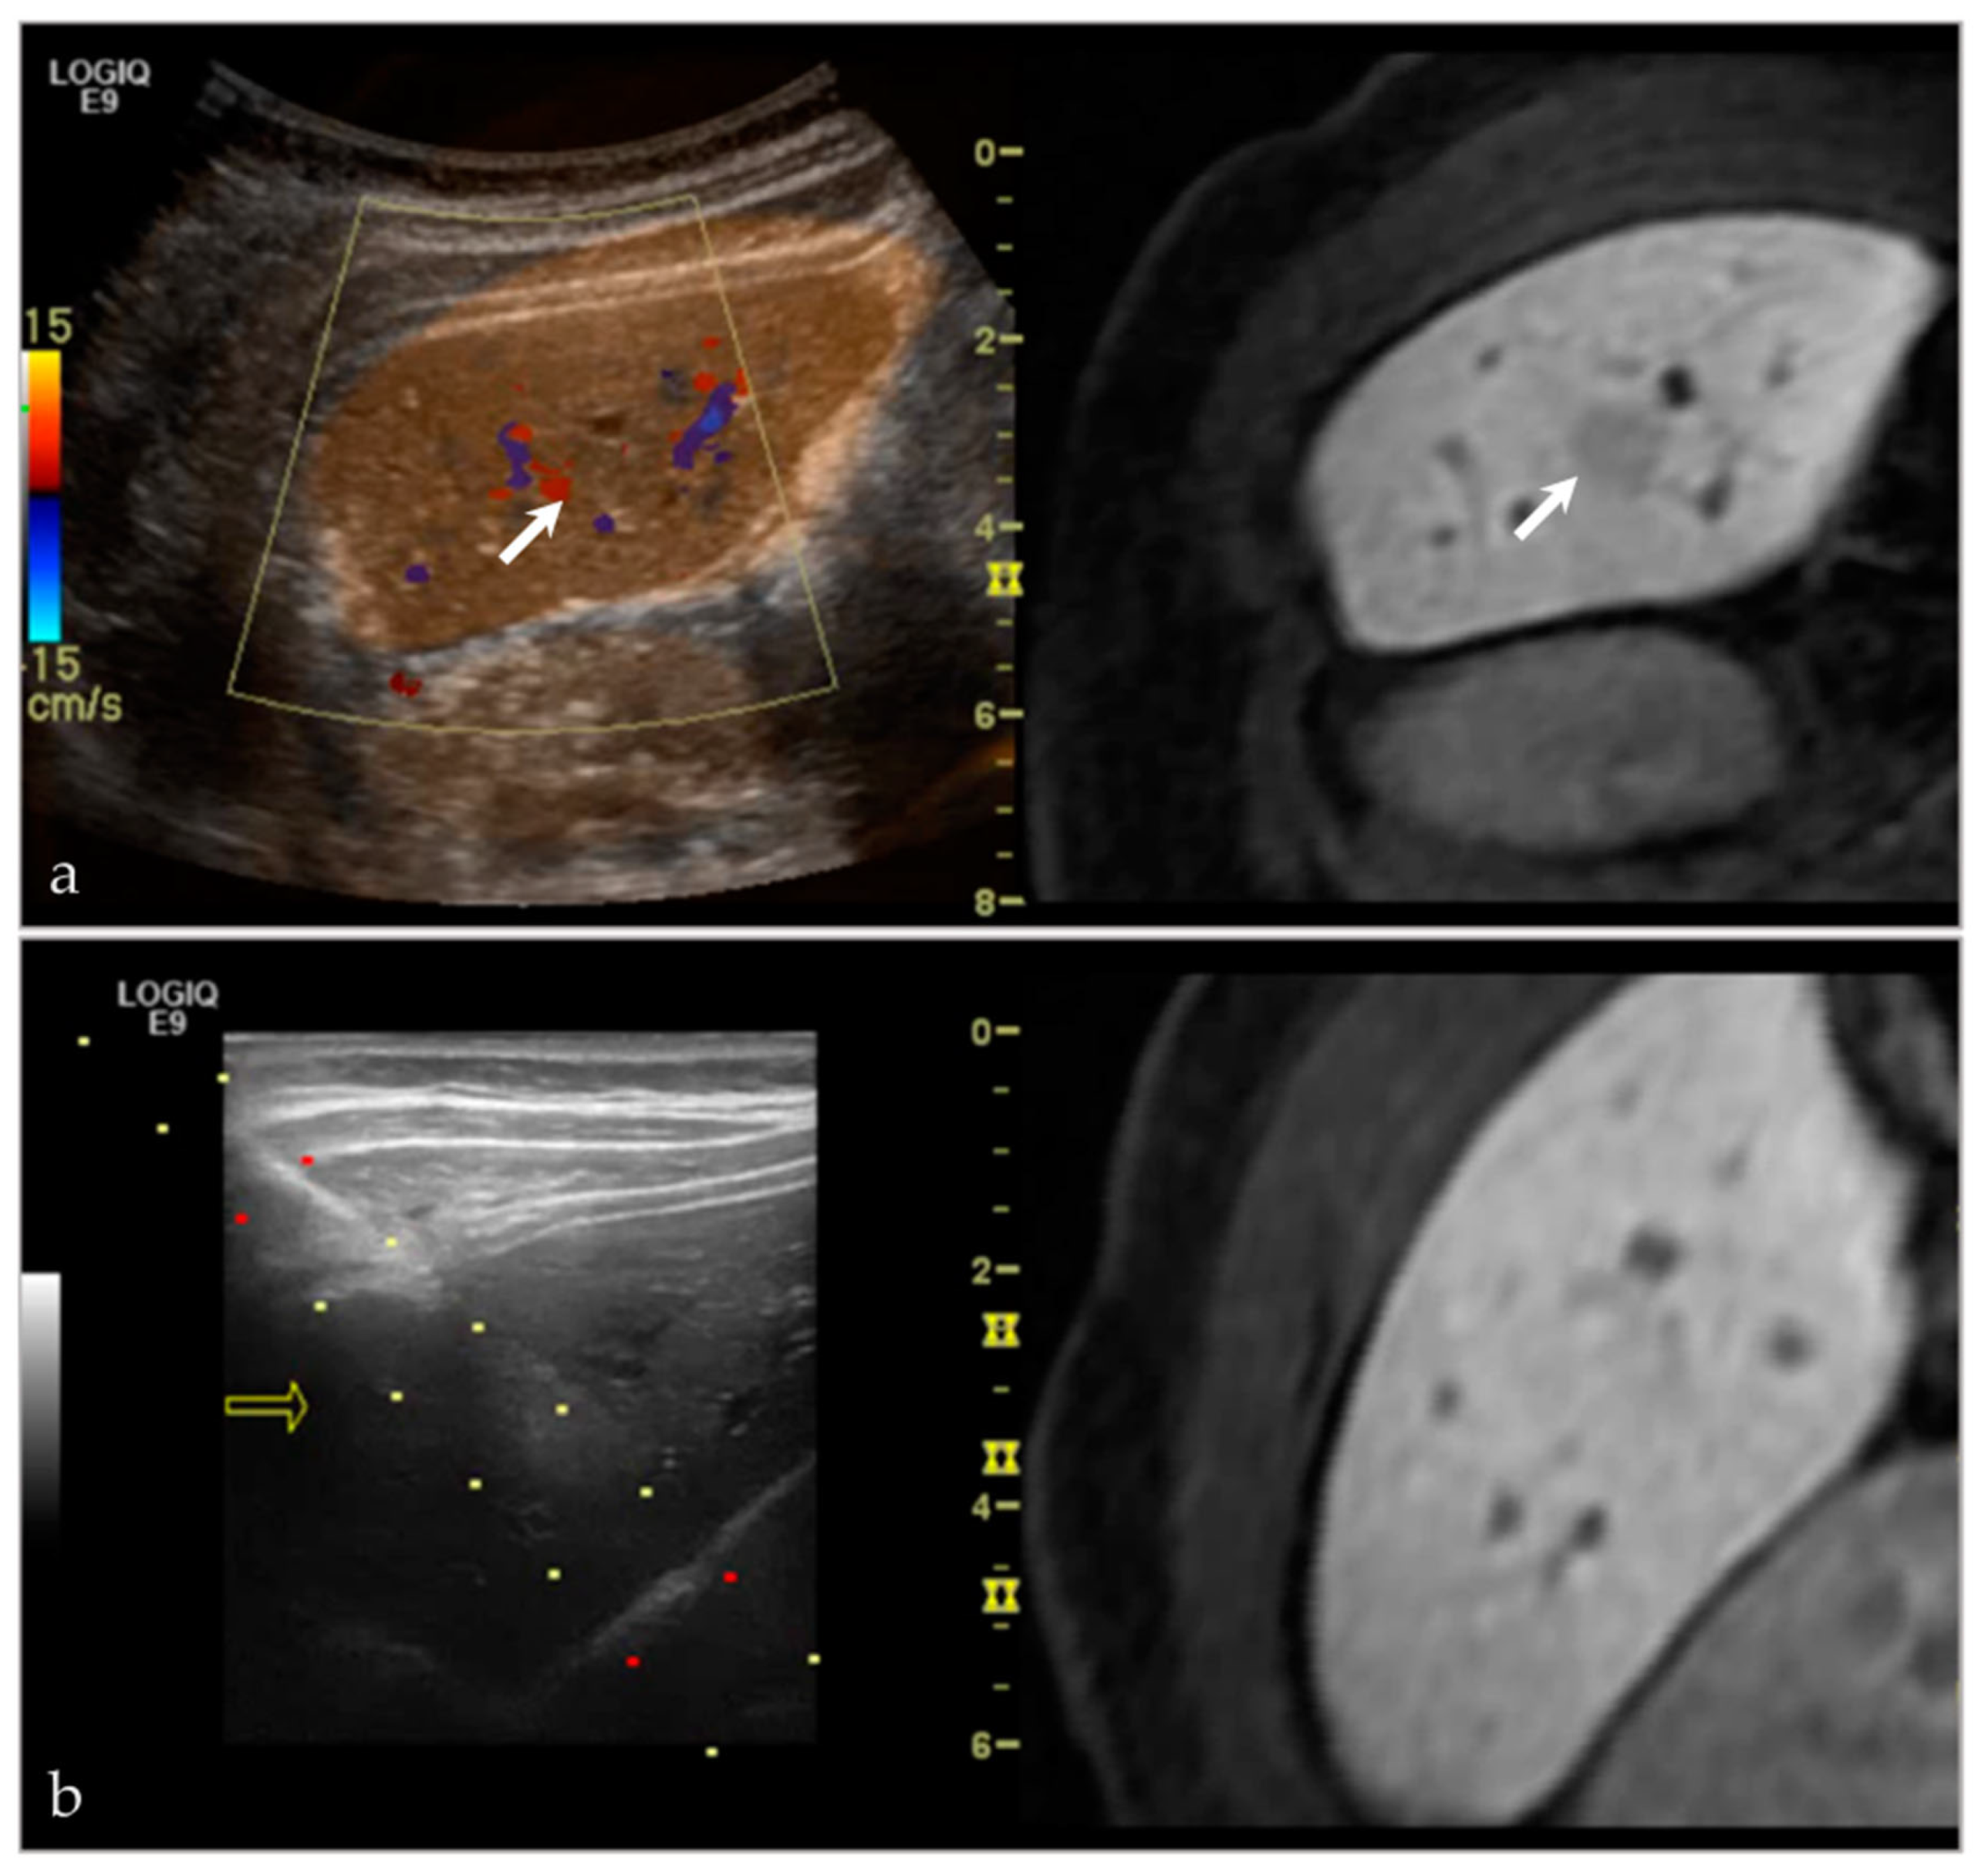

3.2.4. Targeted Percutaneous Lesion Biopsy and/or Aspiration

- Lee, K.H.; Lau, V.; Gao, Y.; Li, Y.L.; Fang, B.X.H.; Lee, R.; Lam, W.W.M. Ultrasound-MRI fusion for targeted biopsy of myopathies. Am. J. Roentgenol. 2019, 212, 1126–1128. [Google Scholar] [CrossRef] [PubMed]

| NA/NA | Left paraspinal region | US-CT | Metastatic disease, unknown carcinoma | Neoplastic, malignant |

| 63/F | Left posterior iliac bone | US-PET | Metastatic disease, breast carcinoma | Neoplastic, malignant |